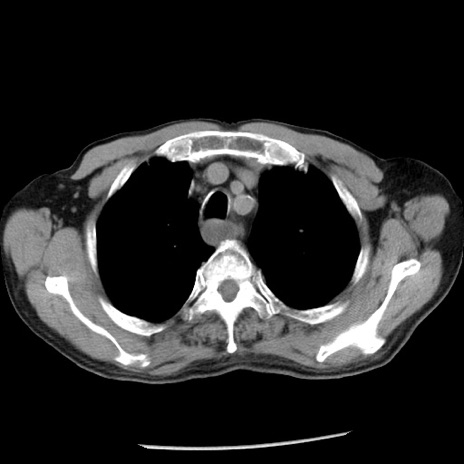

症例26(横断像)

【症例】80歳代男性

【主訴】嘔吐

【現病歴】昨晩2回嘔吐あり、今朝になっても嘔吐あり。来院。

【既往歴】胃潰瘍

【身体所見】意識清明、BT 37.6℃、BP 166/95mmHg、HR 100bpm、SpO2 97%、腹部:平坦・軟、腸蠕動音聴取良好、圧痛なし。

【データ】WBC 21900、CRP 1.46